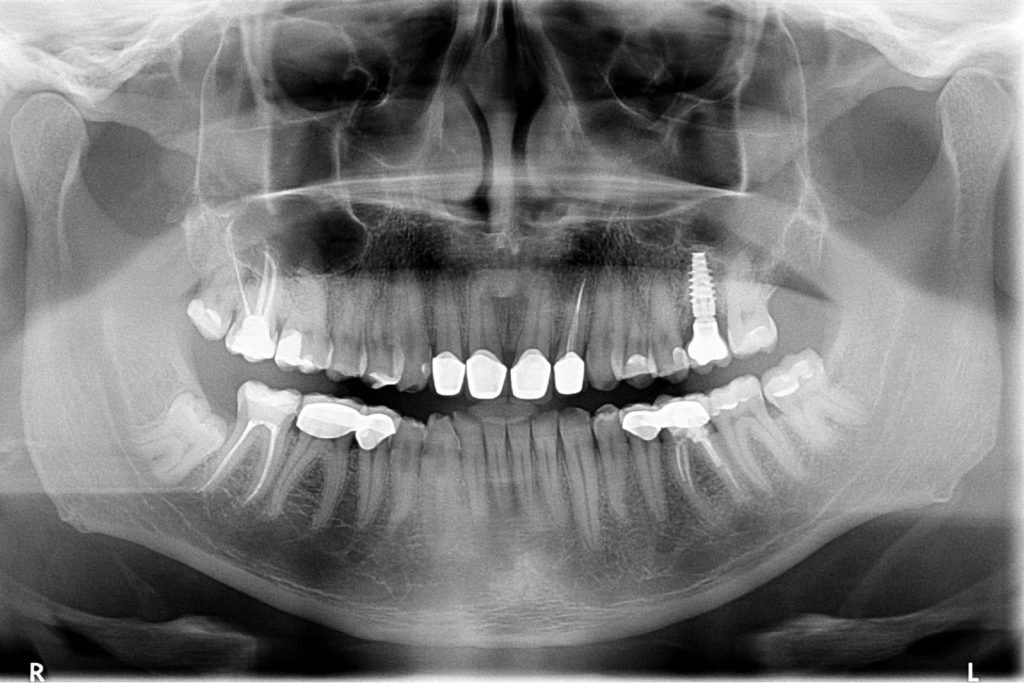

Przed podjęciem leczenia należy określić stopień zaniku kości szczęk oraz żuchwy. W tym celu przeprowadza się badanie kliniczne oraz odpowiednią diagnostykę obrazową pacjenta. Uwzględnia ona zdjęcie panoramiczne OPG jako podstawę dwuwymiarowego obrazowania podłoża kostnego oraz możliwe jest badanie tomograficzne CT lub bardziej precyzyjna tomografia stożkowa CBCT. Opcjonalnie wykorzystywana diagnostycznie tomografia pozwala na bardziej wnikliwą ocenę stopnia zaniku kości w trójwymiarowym, przestrzennym obrazie.

Procedury te są stosowane w sytuacji niedostatecznej ilości kości, skutkującej odsłonięciem gwintu, podczas gdy wszczepiamy implanty stomatologiczne lub też jako zabiegi poprzedzające ich wprowadzenie.​

Zabiegiem, który rozwiązuje ten problem, jest podniesienie dna zatoki szczękowej, czyli odbudowa kostna w okolicy zębów trzonowych. Ubytek kości uzupełniany jest materiałem kościotwórczym, który układany jest pod błoną wyścielającą zatokę szczękową, zwaną membraną Schneidera. Zmniejszając objętość zatoki szczękowej, tworzy się tym samym stabilną strukturę kostną, umożliwiającą zabieg implantacji wszczepów śródkostnych.

Zatoki szczękowe to symetrycznie umieszczone w kościach szczęk przestrzenie powietrzne, posiadające komunikację z jamą nosa. Średnio pojemność zatok wynosi 24 cm3, a ściany wyścielone są błoną śluzową (membrana Schneidera). Dno zatoki szczękowej stanowi wyrostek zębodołowy, w którym umieszczone są zęby, często zlokalizowane tuż pod cienką wyściółką zatoki. Statystycznie najwęższy obszar kostny w tej strefie zlokalizowany jest na wysokości zębodołów pierwszego i drugiego zęba trzonowego.